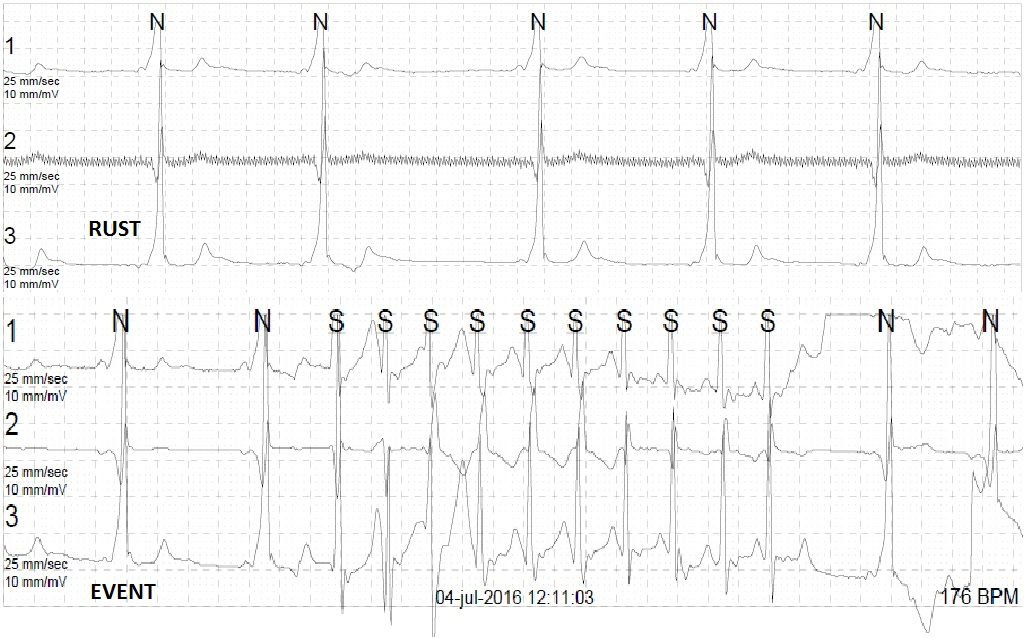

Figuur 2: Holterregistratie met paroxysmale regulaire smalcomplextachycardie 175/min verdacht voor een cirkeltachycardie